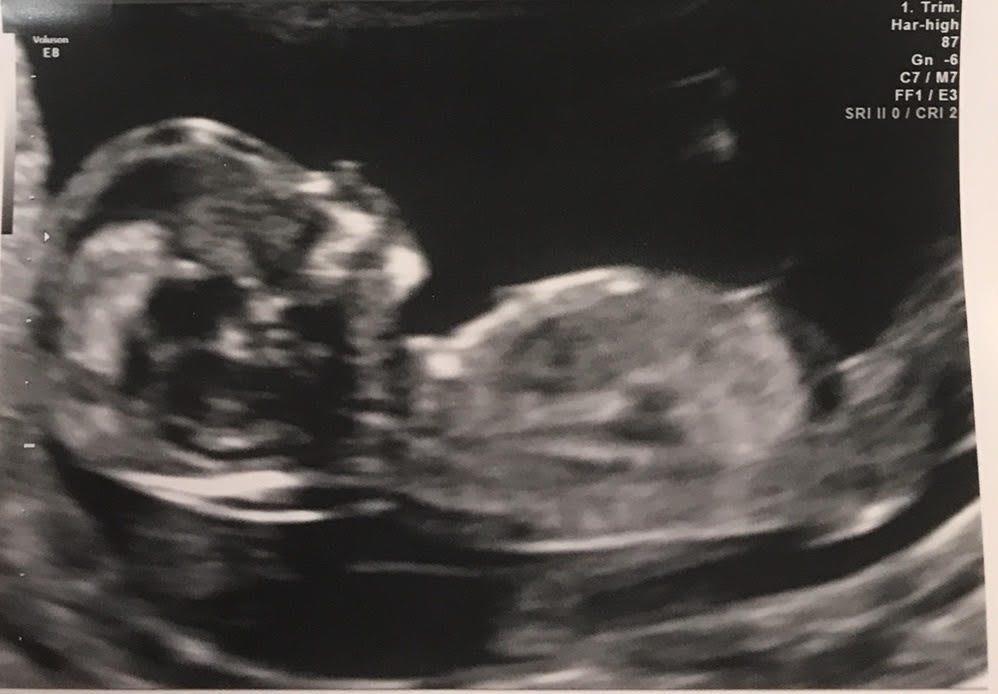

Just had our NT scan at 12 weeks 5 days and would love gender predictions ahead of getting the blood work results back! Have one boy already, swayed pink but with complications so it wasn't a true 100% sway. Thank you ladies in advance! :)Attachment 38839Attachment 38841